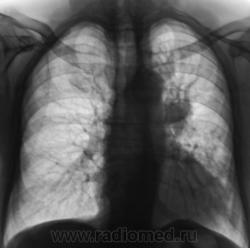

Центральный рак  с ателектазом  S3, на  снимке в прямой проекции то же присутствуют признаки уменьшения объема:  слева  диафрагма расположена выше обычного, средостение смещено влево, несмотря на поворот вправо при установке.

Я не склонен думать , что "это" Его величество Туберкулёз. На мой взгляд - "Сиятельный ТУМОР".

Случай сегодняшний, еще и протокол не написан, так как пациент явился в 15 часов на диагностическую флюорографию, направлен по поводу пнемонии. Давненько, я не видел мокроты цвета "малинового желе", но в данном случае увидел. Лаборатория и прочее - все будет завтра.